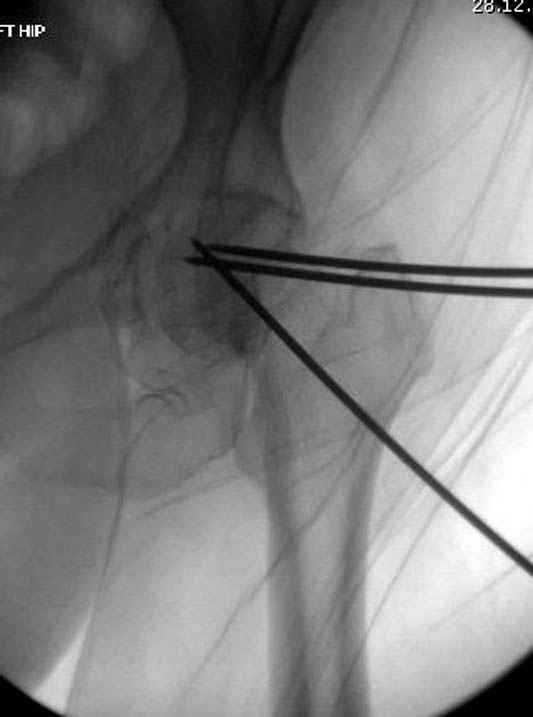

рекомендуется ургентная фиксация шейки в первые сутки, а в дальнейшем таз.

В данный момент скелетное вытяжение поучается через перелом шейки, а фиксированный перелом шейки будет участвовать в процессе вытяжения через каннюлированные шурупы.

Перелом шейки смогли зафиксировать через пару дней, ацетабулум до сих пор не оперирован, на вытяжении.

Фиксацию шейки провели когда получили окно, быстро

перкутанно смогли провести шурупы.